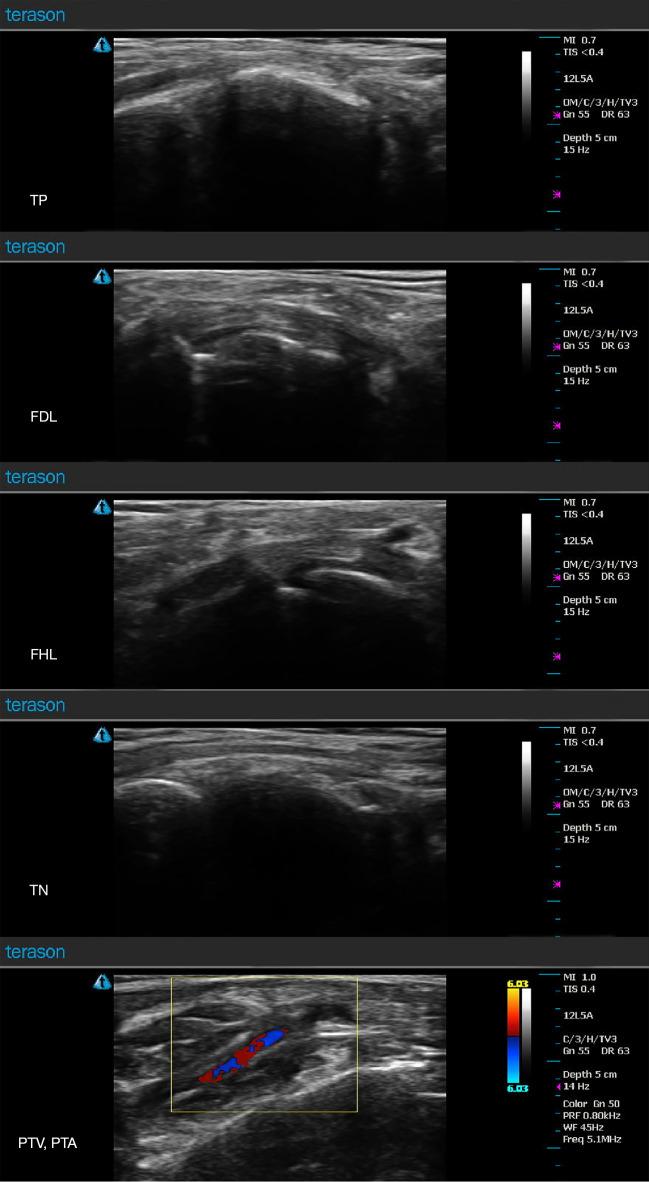

Tarsal tunnel syndrome (TTS) is a condition in which the tibial nerve (TN) (or its terminal branches) is compressed by the flexor retinaculum (FR) and the deep fascia of the abductor hallucis muscle at the tarsal tunnel, causing symptoms that negatively impact the patient's quality of life, including numbness, a sensation of a foreign object, coldness, and pain. FR release via microtrauma using needle-knife has proven to be effective in China and is widely used by clinicians. The traditional acupotomy, however, is the "blind knife" treatment, which cannot guarantee patient safety due to risk of injury to important structures, particularly the neurovascular bundle. Compared with the conventional treatments, ultrasound-guided percutaneous FR release possesses noteworthy advantages including high efficacy and safety.

跗管综合征(TTS)是一种胫神经(TN)(或其终末分支)在跗管处被屈肌支持带(FR)和拇展肌深筋膜压迫的病症,会引发对患者生活质量产生负面影响的症状,包括麻木、异物感、发冷和疼痛。在中国,使用针刀通过微创伤进行FR松解已被证明是有效的,并且被临床医生广泛应用。然而,传统针刀是“盲刀”治疗,由于存在损伤重要结构(特别是神经血管束)的风险,无法保证患者安全。与传统治疗方法相比,超声引导下经皮FR松解具有显著优势,包括高效性和安全性。